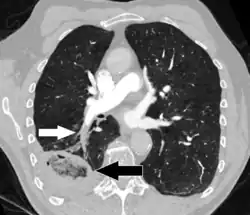

Компьютерная томография инфаркта лёгкого на фоне хронической тромбоэмболии легочной артерии (белая стрелка). Область инфаркта (чёрная стрелка) имеет обратный знак ореола.